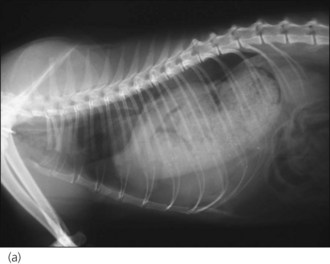

Radiography is commonly used in animals with suspected diaphragmatic rupture and consistent findings include complete or partial loss of the diaphragmatic line, mediastinal shift, obscuring of the cardiac silhouette, and cranial displacement of abdominal viscera and gas shadows (Figures 28.5 and 28.6). Orthogonal views are recommended but diagnosis may be difficult, for example if displaced viscera are obscured by pleural fluid or in the absence of visceral displacement. Positive contrast gastrography or peritoneography may be required in these cases.

image image

Figure 28.5 (a) Right lateral and (b) dorsoventral thoracic radiographs of a cat showing diaphragmatic rupture.

Figure 28.6 (a) Right lateral and (b) dorsoventral thoracic radiographs of a cross-bred dog showing diaphragmatic rupture.